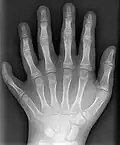

Полидактили́я (др.-греч. πολύς — много + δάκτυλος — палец, синоним — многопалость), также известная как гипердактилия — порок развития, характеризующейся бо́льшим, чем в норме, количеством пальцев на руках или ногах у человека, собак, котов и лошадей. Противоположным отклонением является олигодактилия.

У людей и животных она может проявляться как на одной, так и на обеих руках. Обычно дополнительный палец представляет собой небольшой кусочек мягкой ткани, которую можно удалить. Иногда это просто кость без суставов; очень редко лишний палец бывает полноценным. Дополнительный палец чаще всего образуется со стороны мизинца, реже - на стороне большого пальца и очень редко - между средними пальцами. Обычно лишний палец является аномальным разветвлением обычного пальца, редко возникает на запястье, как обычный палец.